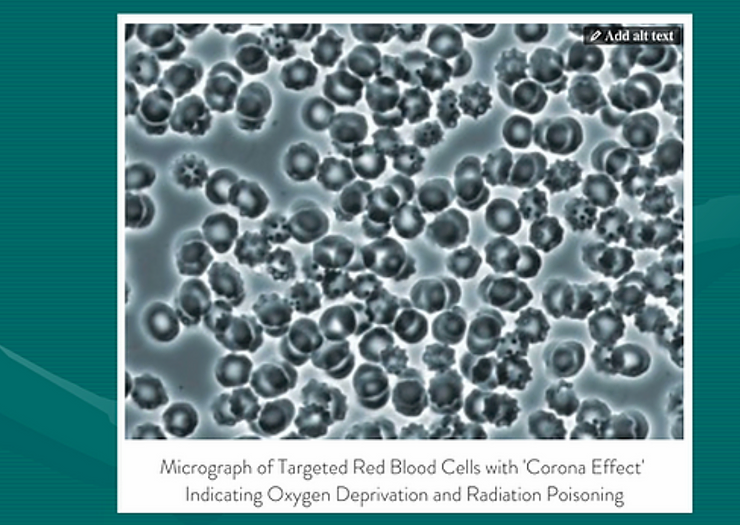

Video 1 Shows the Healthy Normal Activity of a Neutrophil Cleaning the Membranes of Red Blood Cells. You will also see the ‘Corona Effect” or the degeneration of the membrane of the red blood cells showing a crowning with protruding spikes or vesicles. These cells are also known as echinocytes and schistocytes.

In this video 4 of 4 you will see the visual evidence of the ‘Corona Effect’ of the red blood cells which is NOT a viral infectious condition but a degenerative acidic lifestyle condition of the cell membranes due to an acidic biochemistry, an acidic electromagnetic field and an oxygen deprived environment.[2]

These deteriorating red blood cells are the evidence of cellular aging due to a compromised internal environment triggered by how one lives, what one eats, drinks, breathes, thinks, feels and believes.